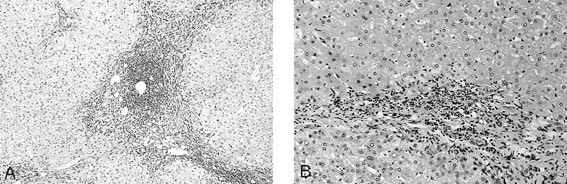

FIGURE 5

Hepatitis C with cirrhosis. A, note the lymphoid aggregate typical of hepatitis C and the rounded nodules of the cirrhosis (25×). B, interface hepatitis at the edge of a nodule for a Grade 2 on a scale of 4 for necroinflammatory activity (50×).